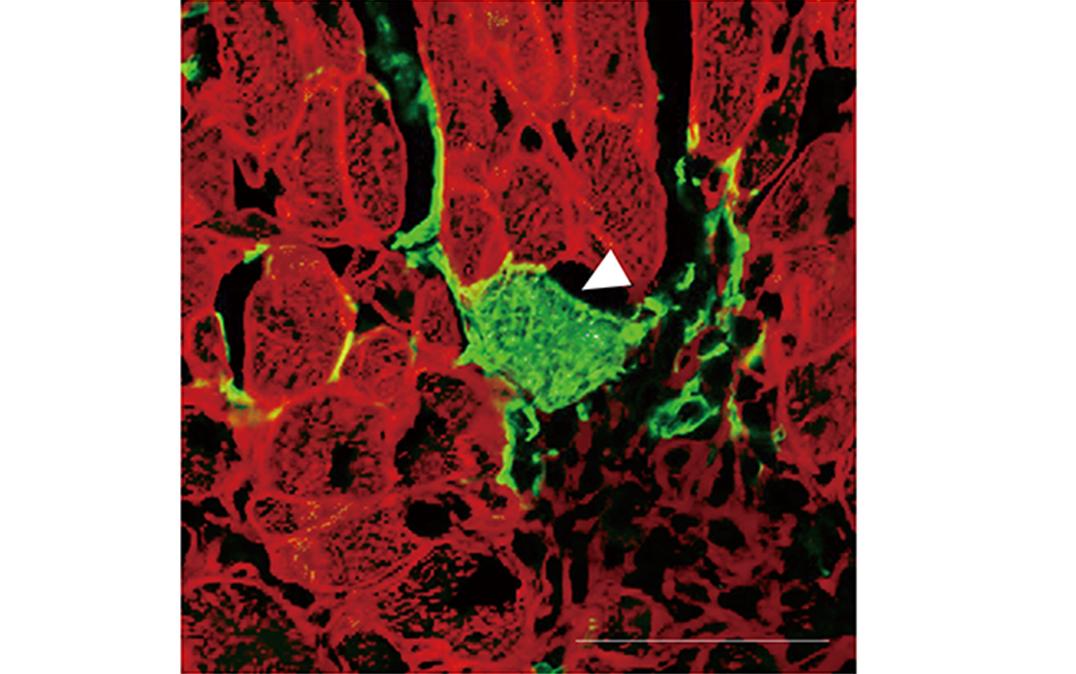

To achieve their goal, the researchers first generated mice in which all cells emitted red fluorescence. However, the mice were modified in a way that the fibroblasts emitted green fluorescence after treatment with the drug tamoxifen. As a result, when looking at the heart after treatment with tamoxifen, cells that emitted both red and green fluorescence indicated that cell fusion between fibroblasts and cardiomyocytes had happened. Conversely, the presence of green fluorescence indicated that direct reprogramming of fibroblasts to cardiomyocytes had occurred.

Equipped with the tools to tackle their research question, the researchers used a mouse model of heart attack and treated the mice with tamoxifen. While there was no direct reprogramming in a control group, the researchers found 1-1.5% of directly reprogrammed cells when a virus carrying cardiac transcription factors was injected into the mice. Both groups exhibited minimal cell fusion. These results suggest that the main route of generating new heart muscle cells by this method is via reprogramming fibroblasts directly to cardiomyocytes.